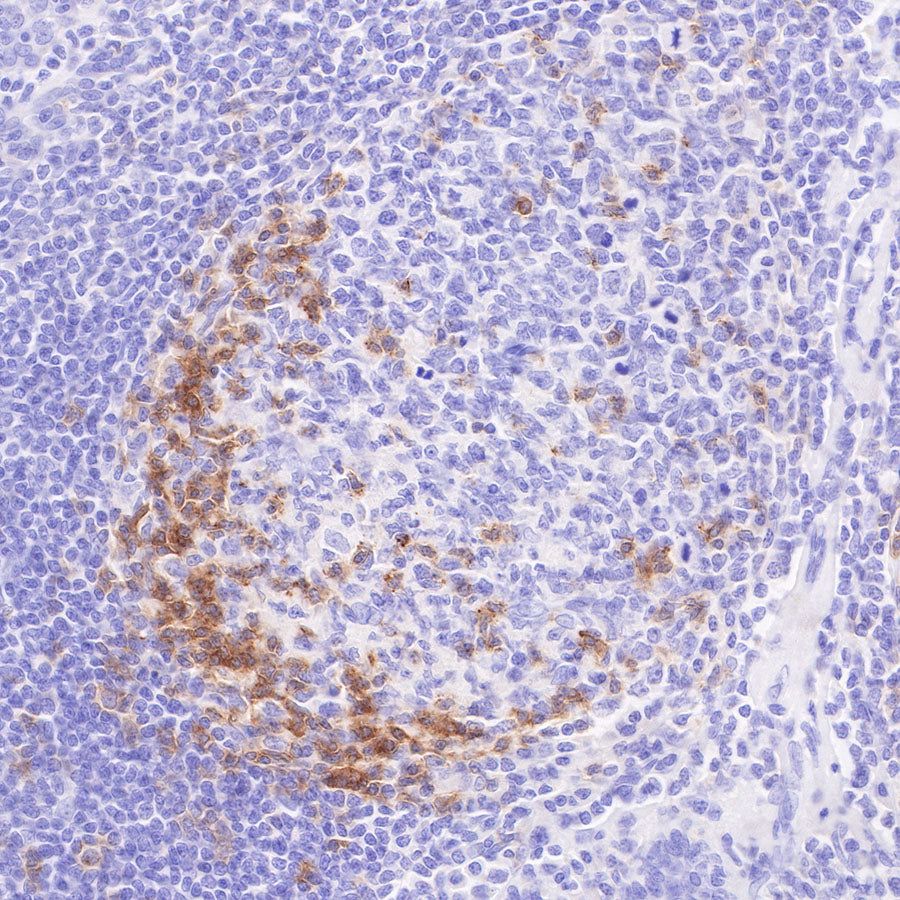

Immunohistochemistry

IHC shows positive staining in paraffin-embedded human tonsil. Anti-PD-1 antibody was used at 1/200 dilution, followed by a HRP Polymer for Mouse & Rabbit IgG (ready to use). Counterstained with hematoxylin. Heat mediated antigen retrieval with Tris/EDTA buffer pH9.0 was performed before commencing with IHC staining protocol.

IHC shows positive staining in paraffin-embedded human spleen. Anti-PD-1 antibody was used at 1/500 dilution, followed by a HRP Polymer for Mouse & Rabbit IgG (ready to use). Counterstained with hematoxylin. Heat mediated antigen retrieval with Tris/EDTA buffer pH9.0 was performed before commencing with IHC staining protocol.